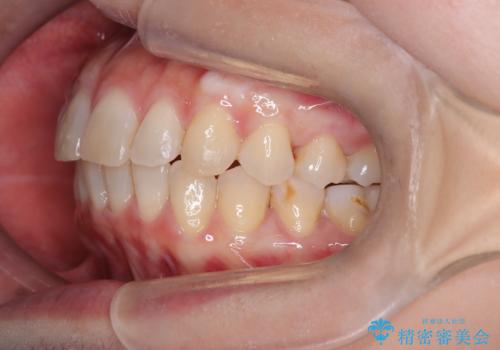

【インビザライン】前歯の凸凹を治したい

- 前歯の凸凹を主訴に来院されました。

臼歯部の遠心移動を行いながらスペースを作り、インビザラインにて前歯をきれいに並べることができました。

今回の治療計画では臼歯部の遠心移動とIPRを行っています。